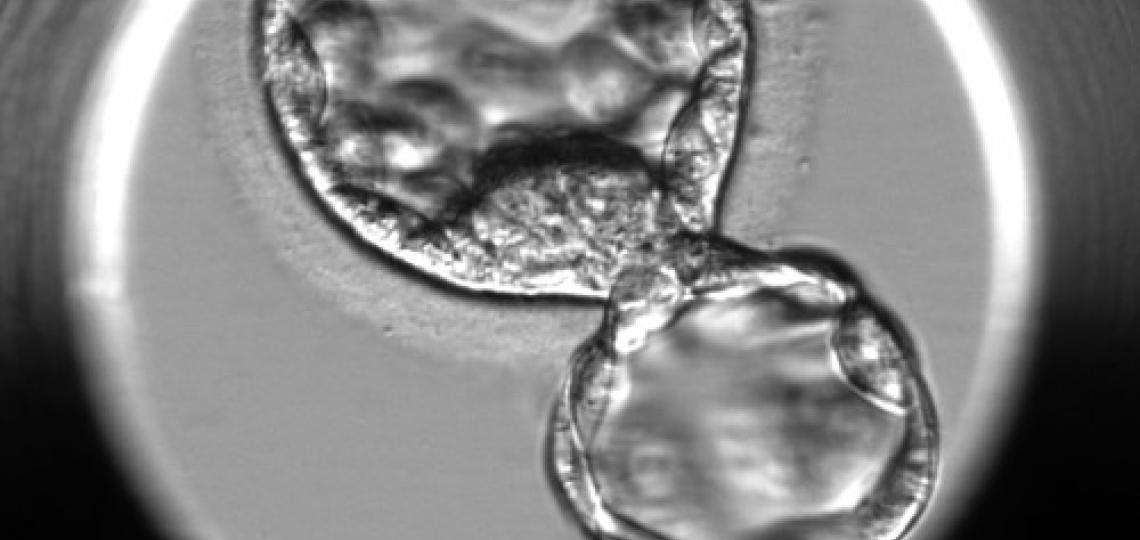

Sharif M, Anvar Z, Chakchouk I, El-Dessouky SH, Zemet R, Kao EC, Sharaf-Eldin WE, Wan YW, Liu Z, Liu P, Jochum M, Van den Veyver IB. Loss of the Maternal Effect Gene NLRP2 Impairs Embryonic and Extra-Embryonic Development, Revealing a Novel Genetic Cause of Congenital Anomalies. Biol Reprod. 2025 Dec 27:ioaf290. doi: 10.1093/biolre/ioaf290. Online ahead of print.PMID: 41454780